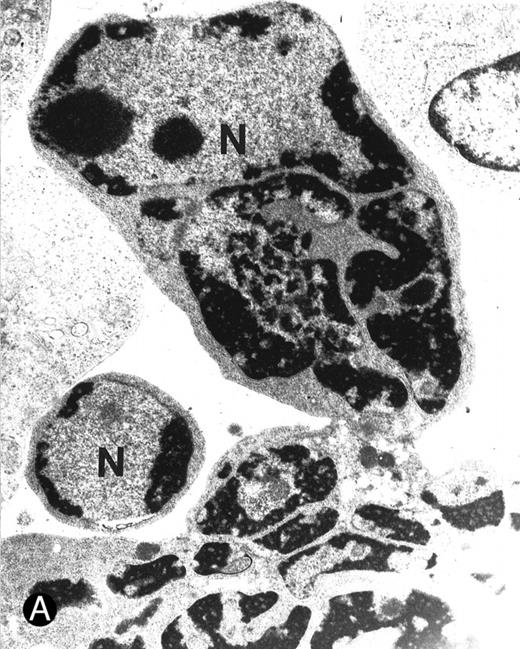

Ultrastructural examination of apoptotic SupT1 cells by transmission electron microscopy (8 day pi). In (A), two apoptotic nuclei in cells that do not show viral particles.

In (B), note the presence of empty capsids (asterisk) in the cytoplasm of an apoptotic cell (see also the insert at the top left). All cells show chromatin condensation, a characteristic feature of apoptosis. N, nucleus; cy, cytoplasm. Original magnifications: (A) ×4,400 and (B) ×8,800; insert in (B) ×40,000.

Absence of mature virions in apoptotic SupT1 cells. Although the findings given above suggested that an increased viral load was causally related to the induction of apoptotic cell death, we had no information on whether productive HHV-7 infection directly induced apoptotic cell death or whether this effect was indirectly mediated by HHV-7 gene products or by soluble factors released by infected cells. We approached this problem in next group of experiments by analyzing the presence of HHV-7 virions in cells with an apoptotic morphology by transmission electron microscopy (Fig 6A and B and Table 2).

It is notable that most cells showing the characteristic morphologic features of apoptosis at the ultrastructural analysis did not show the presence of virions in either the nuclear or the cytoplasmic compartments (Fig 6A). On the other hand, in about 25% of the cells examined it was possible to document the anomalous presence of empty viral capsids in the cytoplasmic compartment (Fig 6B). Because the assembly of nucleocapsids occurs within the nucleus,27 28 these empty cytoplasmic capsids suggested the presence of abortive virus assembly in some apoptotic cells. Table 2 reports the data from the analysis of 100 apoptotic cells, which were randomly obtained from two different infection experiments.